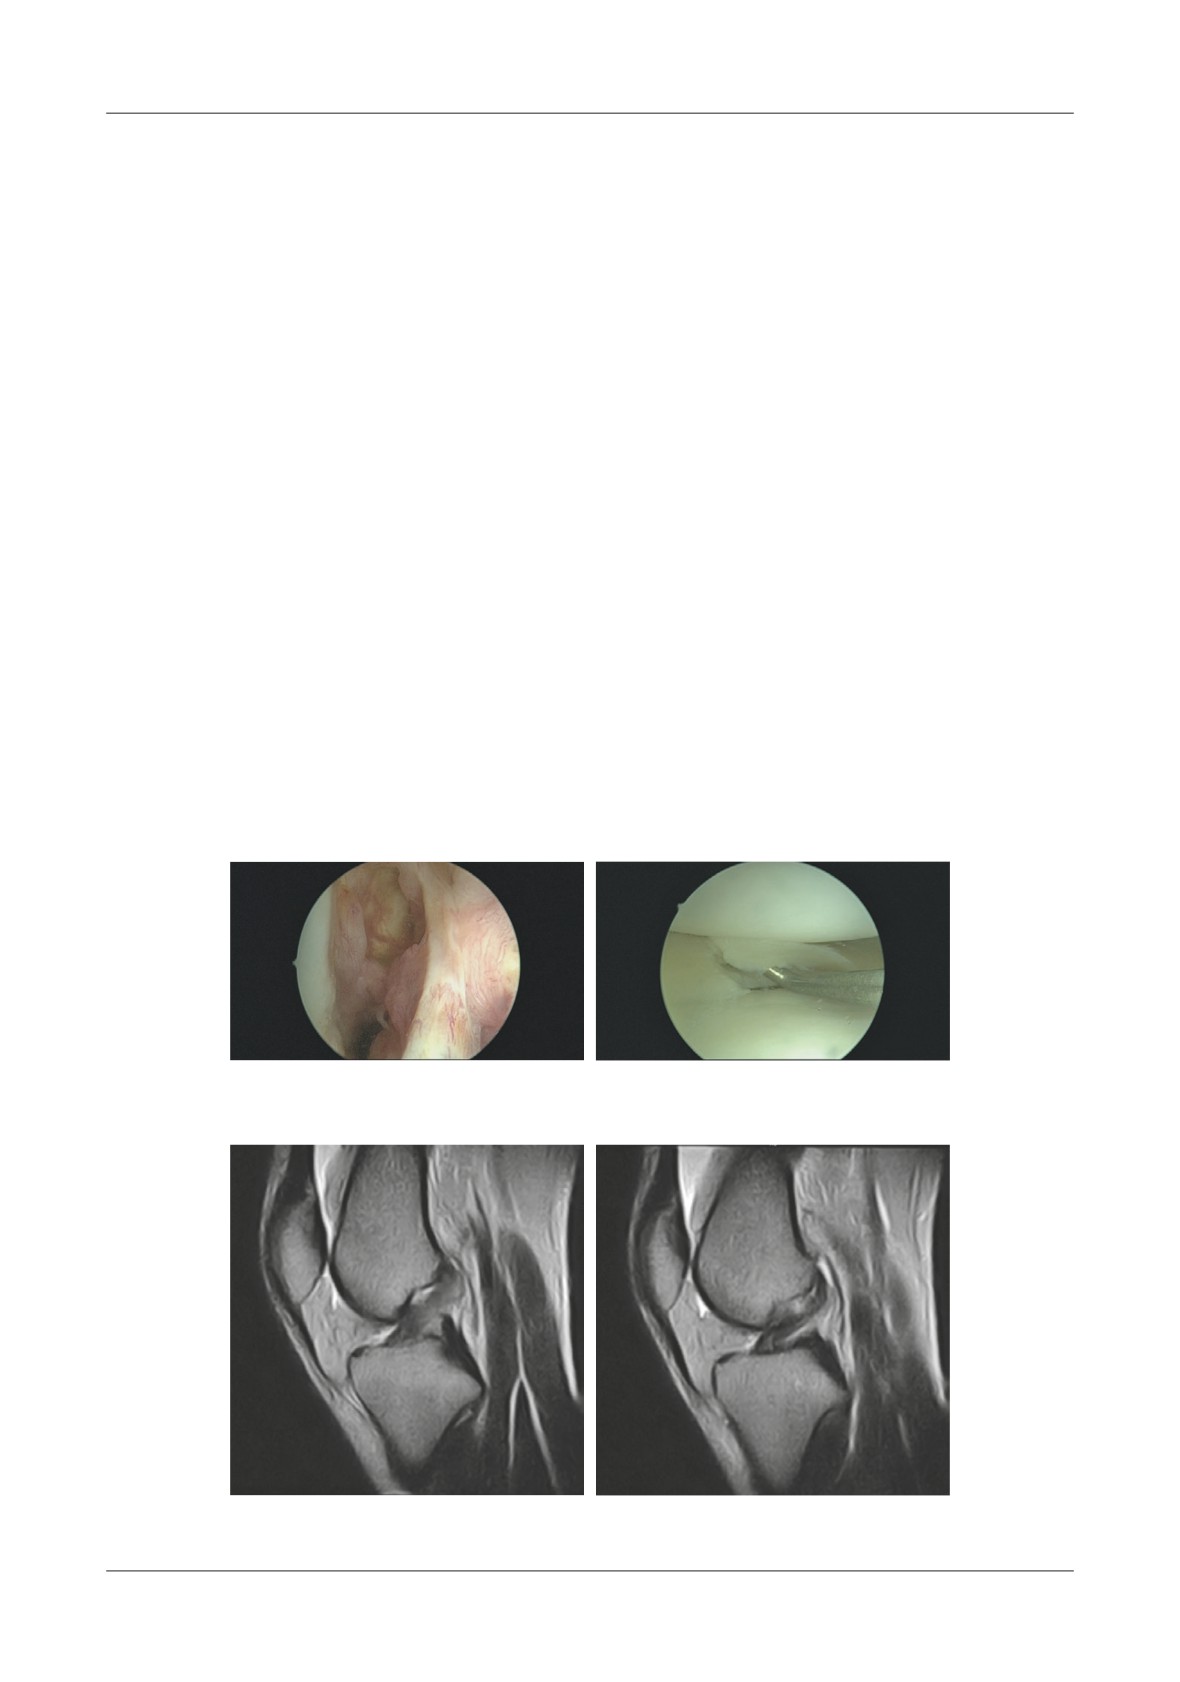

DIAGNOSTIC ACCURACY OF OPEN MRI FOR MENISCAL TEARS

IN ACL DEFICIENT KNEES

We analyzed the current diagnostic accuracy of

open MRI in detecting clinically relevant lesions for

Introduction

patients undergoing ACL reconstruction. Te analysis

included data from 10 females and 43 males with a

Injury of the anterior cruciate ligament of the knee

mean age of 28 years. All had ACL reconstruction and

(ACL) is highly prevalent in the active adult population.

preoperative MRIs done using a 0.22T scanner. For

Te time from injury to orthopedic and magnetic

internal meniscus the preoperative MRI showed true

resonance imaging

(MRI) examination is highly

positive prediction (Crues III) in 14 situations and false

variable. Terefore, at the time of operative treatment

negatives in 1. We excluded incomplete tears (2) and

the patient may have clinically significant concurrent

meniscectomies

(3) and obtained one false positive

meniscal and chondral pathology. A proper preoperative

and32 true negatives

(Crues

0-II).For the external